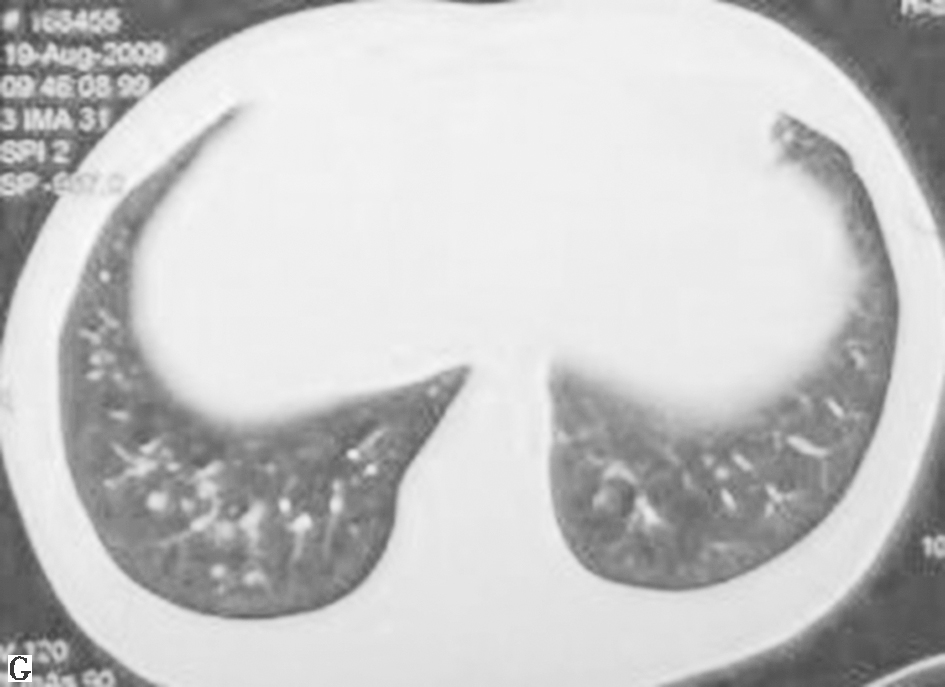

鉴于患者临床症状不重,无肺外系统受累,建议患者严格戒烟(包括被动吸烟)。患者在严格戒烟1个月后,症状逐渐减轻;3个月后复查胸部CT见双肺结节及空洞明显减少(图3);严格戒烟6个月后复查胸部CT显示双肺散在微小结节进一步减轻、减少(图4)。

图4严格戒烟6个月后复查胸部CT表现